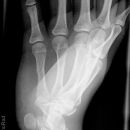

Hand / Handgelenk